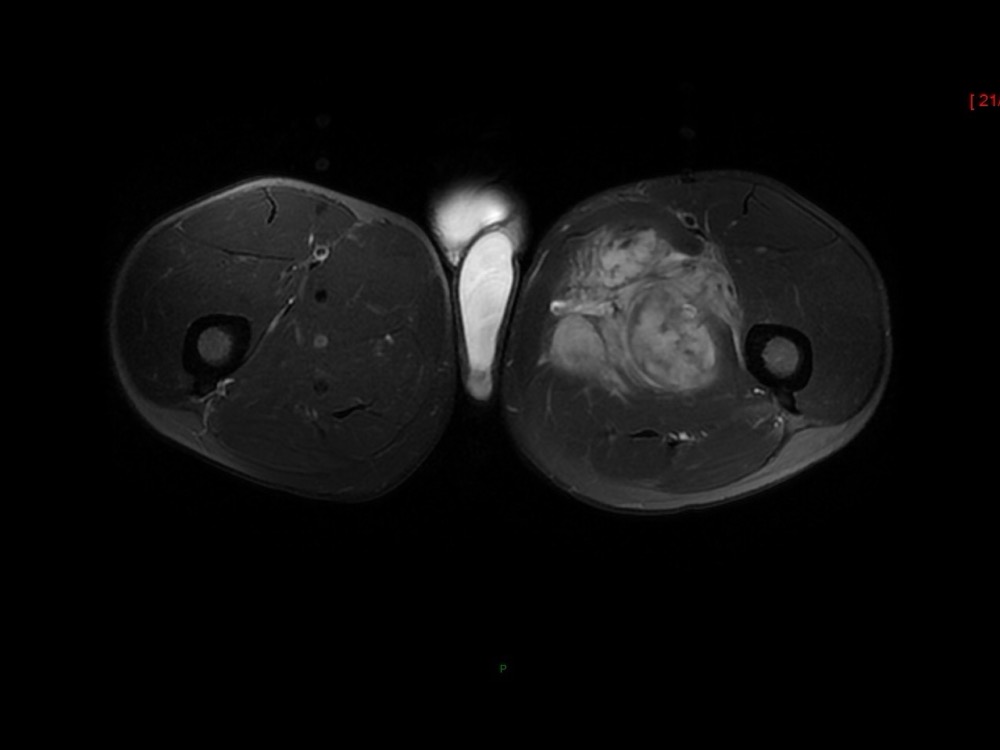

Moalla / Mihoubi-Bouvier / Drapé 18/05/2022